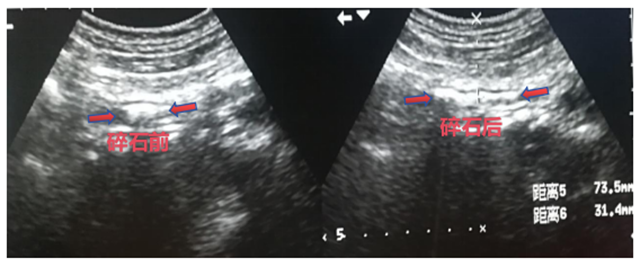

【围观】啪……就碎了……

啪……体外碎石治疗室里传来一阵规律的节奏声,患者还清醒八醒的,是在干什么?  “哦哟,听到那个声音就觉得痛!”  原来是在做体外冲击波碎石治疗(ESWL),它能利用高能冲击波将结石击碎,使其变成小颗粒,通过彩超定位可以观察到结石逐渐碎裂排...